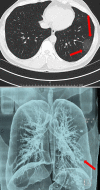

Effectiveness of Computed Tomography in the Diagnosis of Novel Coronavirus-2019

Coronaviruses (CoV) belong to the coronavirus genus of the coronaviridae family. All CoVs are pleomorphic RNA viruses containing crown-like peplomers of 80-160 nm in size. This virus is a zoonotic pathogen seen with a wide range of clinical features from asymptomatic state to intensive care in humans. So far, seven human coronaviruses have been identified with the last one being Coronavirus-2019 (COVID-19). These pathogens typically lead to mild disease, but SARS and MERS type coronaviruses have caused severe respiratory disease and even mortality within the last 20 years. COVID-19 virus has rapidly spread worldwide after China and is continuing to cause huge economical and social impacts. Given the scarcity of resources including healthcare staff, hospital capacities, test kits, etc., timely diagnosis and treatment of this virus are of paramount importance. However, there is no vaccination or drug developed for the treatment of this disease up to today. Because the spreading rate of the virus is very high worldwide and there is no definitive treatment, diagnosis becomes even more important. The objective of this review is to evaluate the use of chest computed tomography, one of the commonly used radiologic imaging modalities, in the diagnosis of COVID-19 in light with the current literatüre.